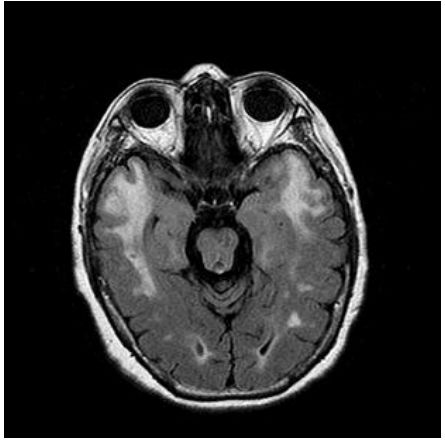

74.55 歲男性由於認知功能退化到精神科求診,根據所附頭部磁振造影(MRI)影像,下列何者為最可能的診斷?

(A)阿茲海默症(Alzheimer's disease) (B)額顳葉失智症(frontotemporal dementia) (C)路易氏體失智症(dementia withLewy bodies) (D)血管性失智症(vascular dementia)